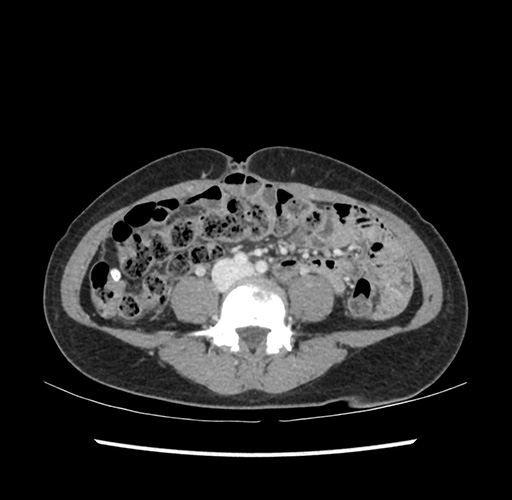

Imaging Analysis

Look through the patient's CT scan to identify any areas of concern for the necessary procedure.

Based on your CT findings, which issue(s) would give reason for "planned slowing down moment(s)" in this case?

Considering a standard left lateral sectionectomy procedure, what step(s) of the operation would you do differently in this case ?